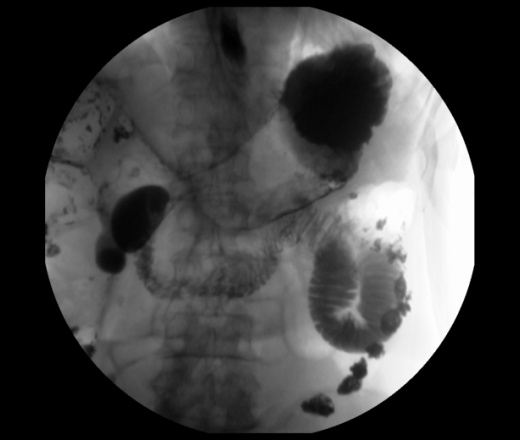

Мужчина 73 года. Жалобы на сниженный аппетит, слабость. Исследование выполенено через несколько дней после ирригоскопии. По результатам ЭФГДС гастрит.

Угол желудка развернут, ригиден. Стойкое циркулярное сужение антрального отдела.Перистальтики нет. Складки прослеживаются.

Эндофитный C-r антрального отдела.